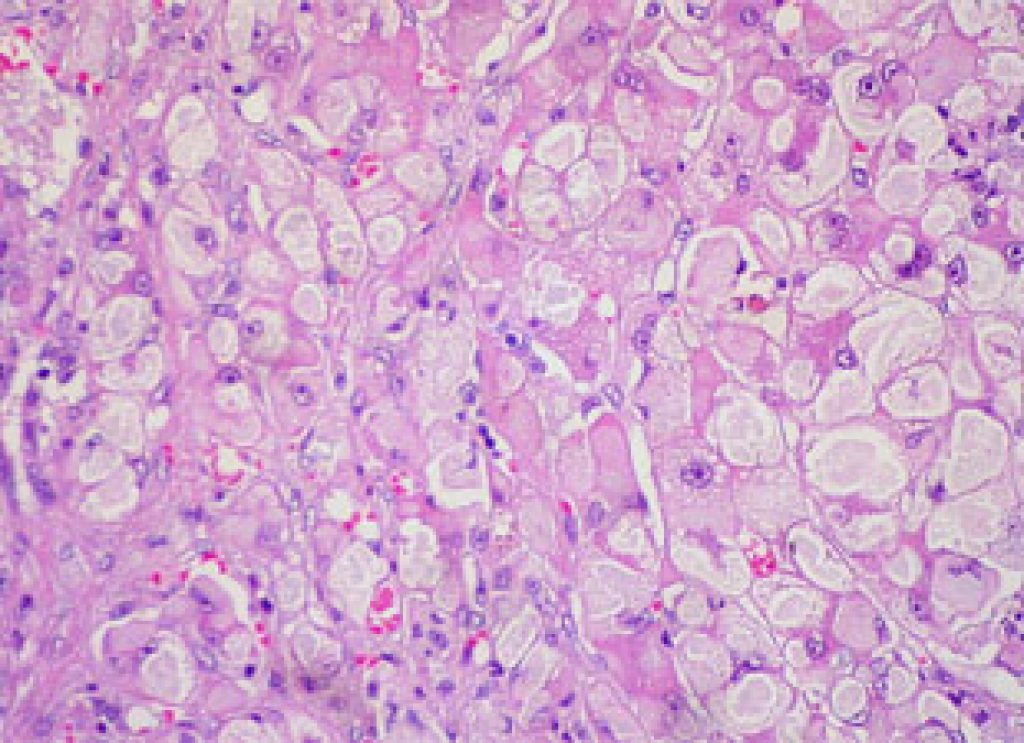

The authors found that the presence of the hepatitis virus in the liver stimulated the release of exosomes from infection-resistant liver resident cells such as Kupffer cells and transmitted them to virus-susceptible liver cells (hepatocytes).

Source: NPG; Photo: euthman/Flickr/CC.